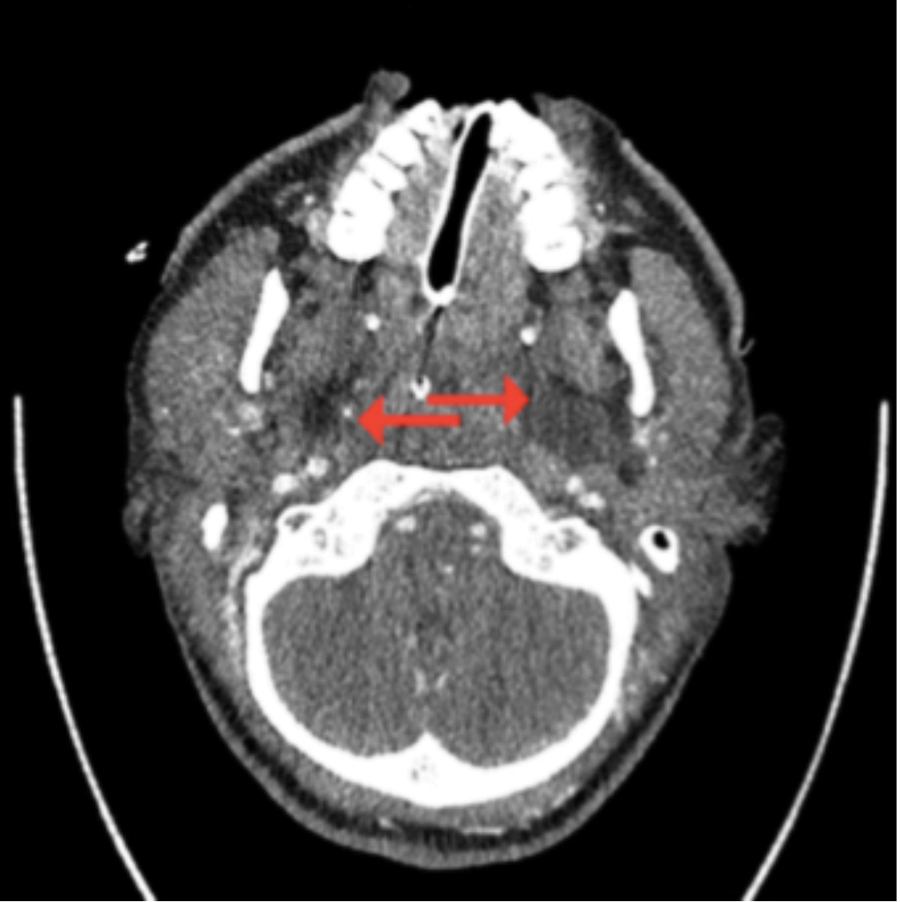

Temporal Space Abscess Misdiagnosed As Temporal Arteritis: A Case Report

Introduction Temporal space abscesses are rare deep neck infections1 that can easily create challenges in diagnosis. Early presenting symptoms of persistent and unrelenting facial pain and trismus have been misdiagnosed as temporomandibular joint dysfunction,2,3,4,5 parotitis,2,3,5,6 trigeminal neuralgia5,7 and diabetic neuropathy in uncontrolled diabetes.5 A temporal space abscess caused by a neck abscess from an attempted … Read more